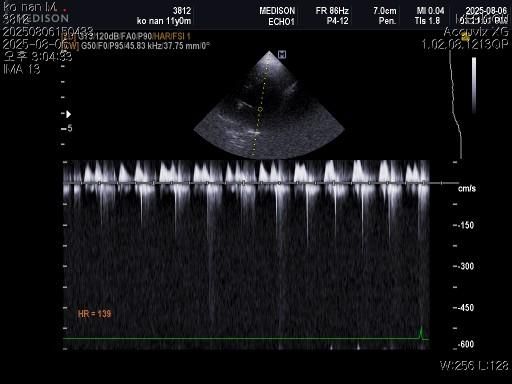

강아지 혈뇨의 원인을 찾고 있습니다 저희 강아지 두번도 아니고 딱 한번만 살려주세요..

1) 혈액검사와 엑스레이 그리고 초음파상 혈뇨의 원인이 나타나지가 않는지 궁금합니다.

3) 신장결석이 어느정도인지도 궁금합니다.